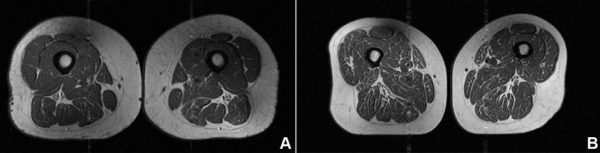

У 61-летней женщины, рацион которой на 29,5% состоял из ультрапереработанных продуктов (A на изображении ниже), индекс массы тела (ИМТ) был немного выше — 32,6, а показатель физической активности — значительно ниже, чем у женщины (B на изображении) с ИМТ 31,8, чей рацион на 87,1% состоял из ультрапереработанных продуктов. Однако у женщины с более высоким показателем потребления ультрапереработанных продуктов наблюдалось значительно больше жировых прожилок на бедрах.

Рацион питания женщины слева на 29,5% состоял из продуктов ультрапереработанной переработки, а рацион питания женщины справа — на 87,1%. (Радиологическое общество Северной Америки)